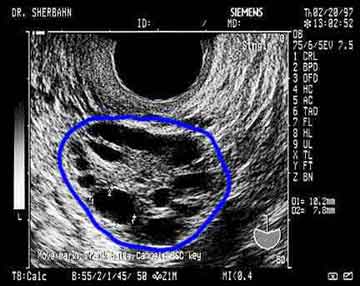

السلام عليكم ارتأيت وانا الاحظ ان المتاخرات في الحمل كثر ان نخصص هدا القسم لنعالج موضوع تكيس المبايض ونستافدو من بعضياتنا

اولا انا عندي تكيس مبايض وهادي عامين باش مزوجة ومازال ما كتاب الحمل انا الان بصدد اخد علاج هرموني وانتظر فرج الله